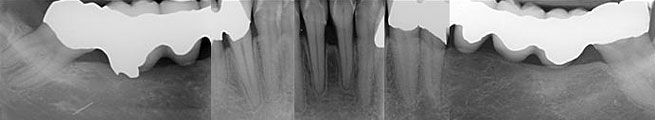

Abb. 1b: Röntgenstatus vom 14. Juli 2009

Abbildung 1: Radiologisch liegen folgende Diagnosen vor: Insuffiziente Wurzelfüllungen an 18,17,21,26, Beherdung an 21, zervikale Karies an 17,11, enge Wurzelproximität an 18,17, Tiefer intraalveolärer Knochendefekt an 25,26.